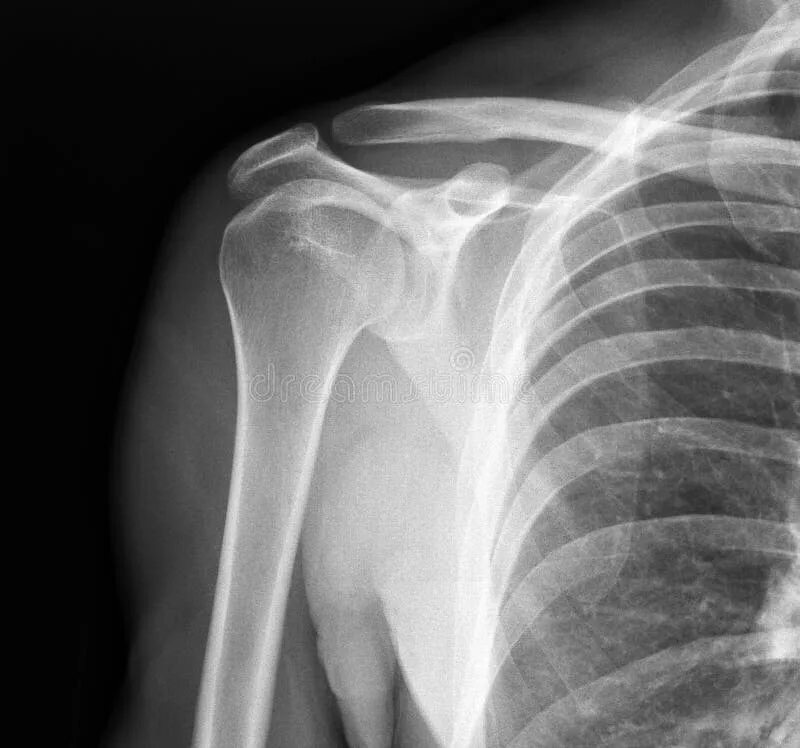

Плечевой сустав у детей